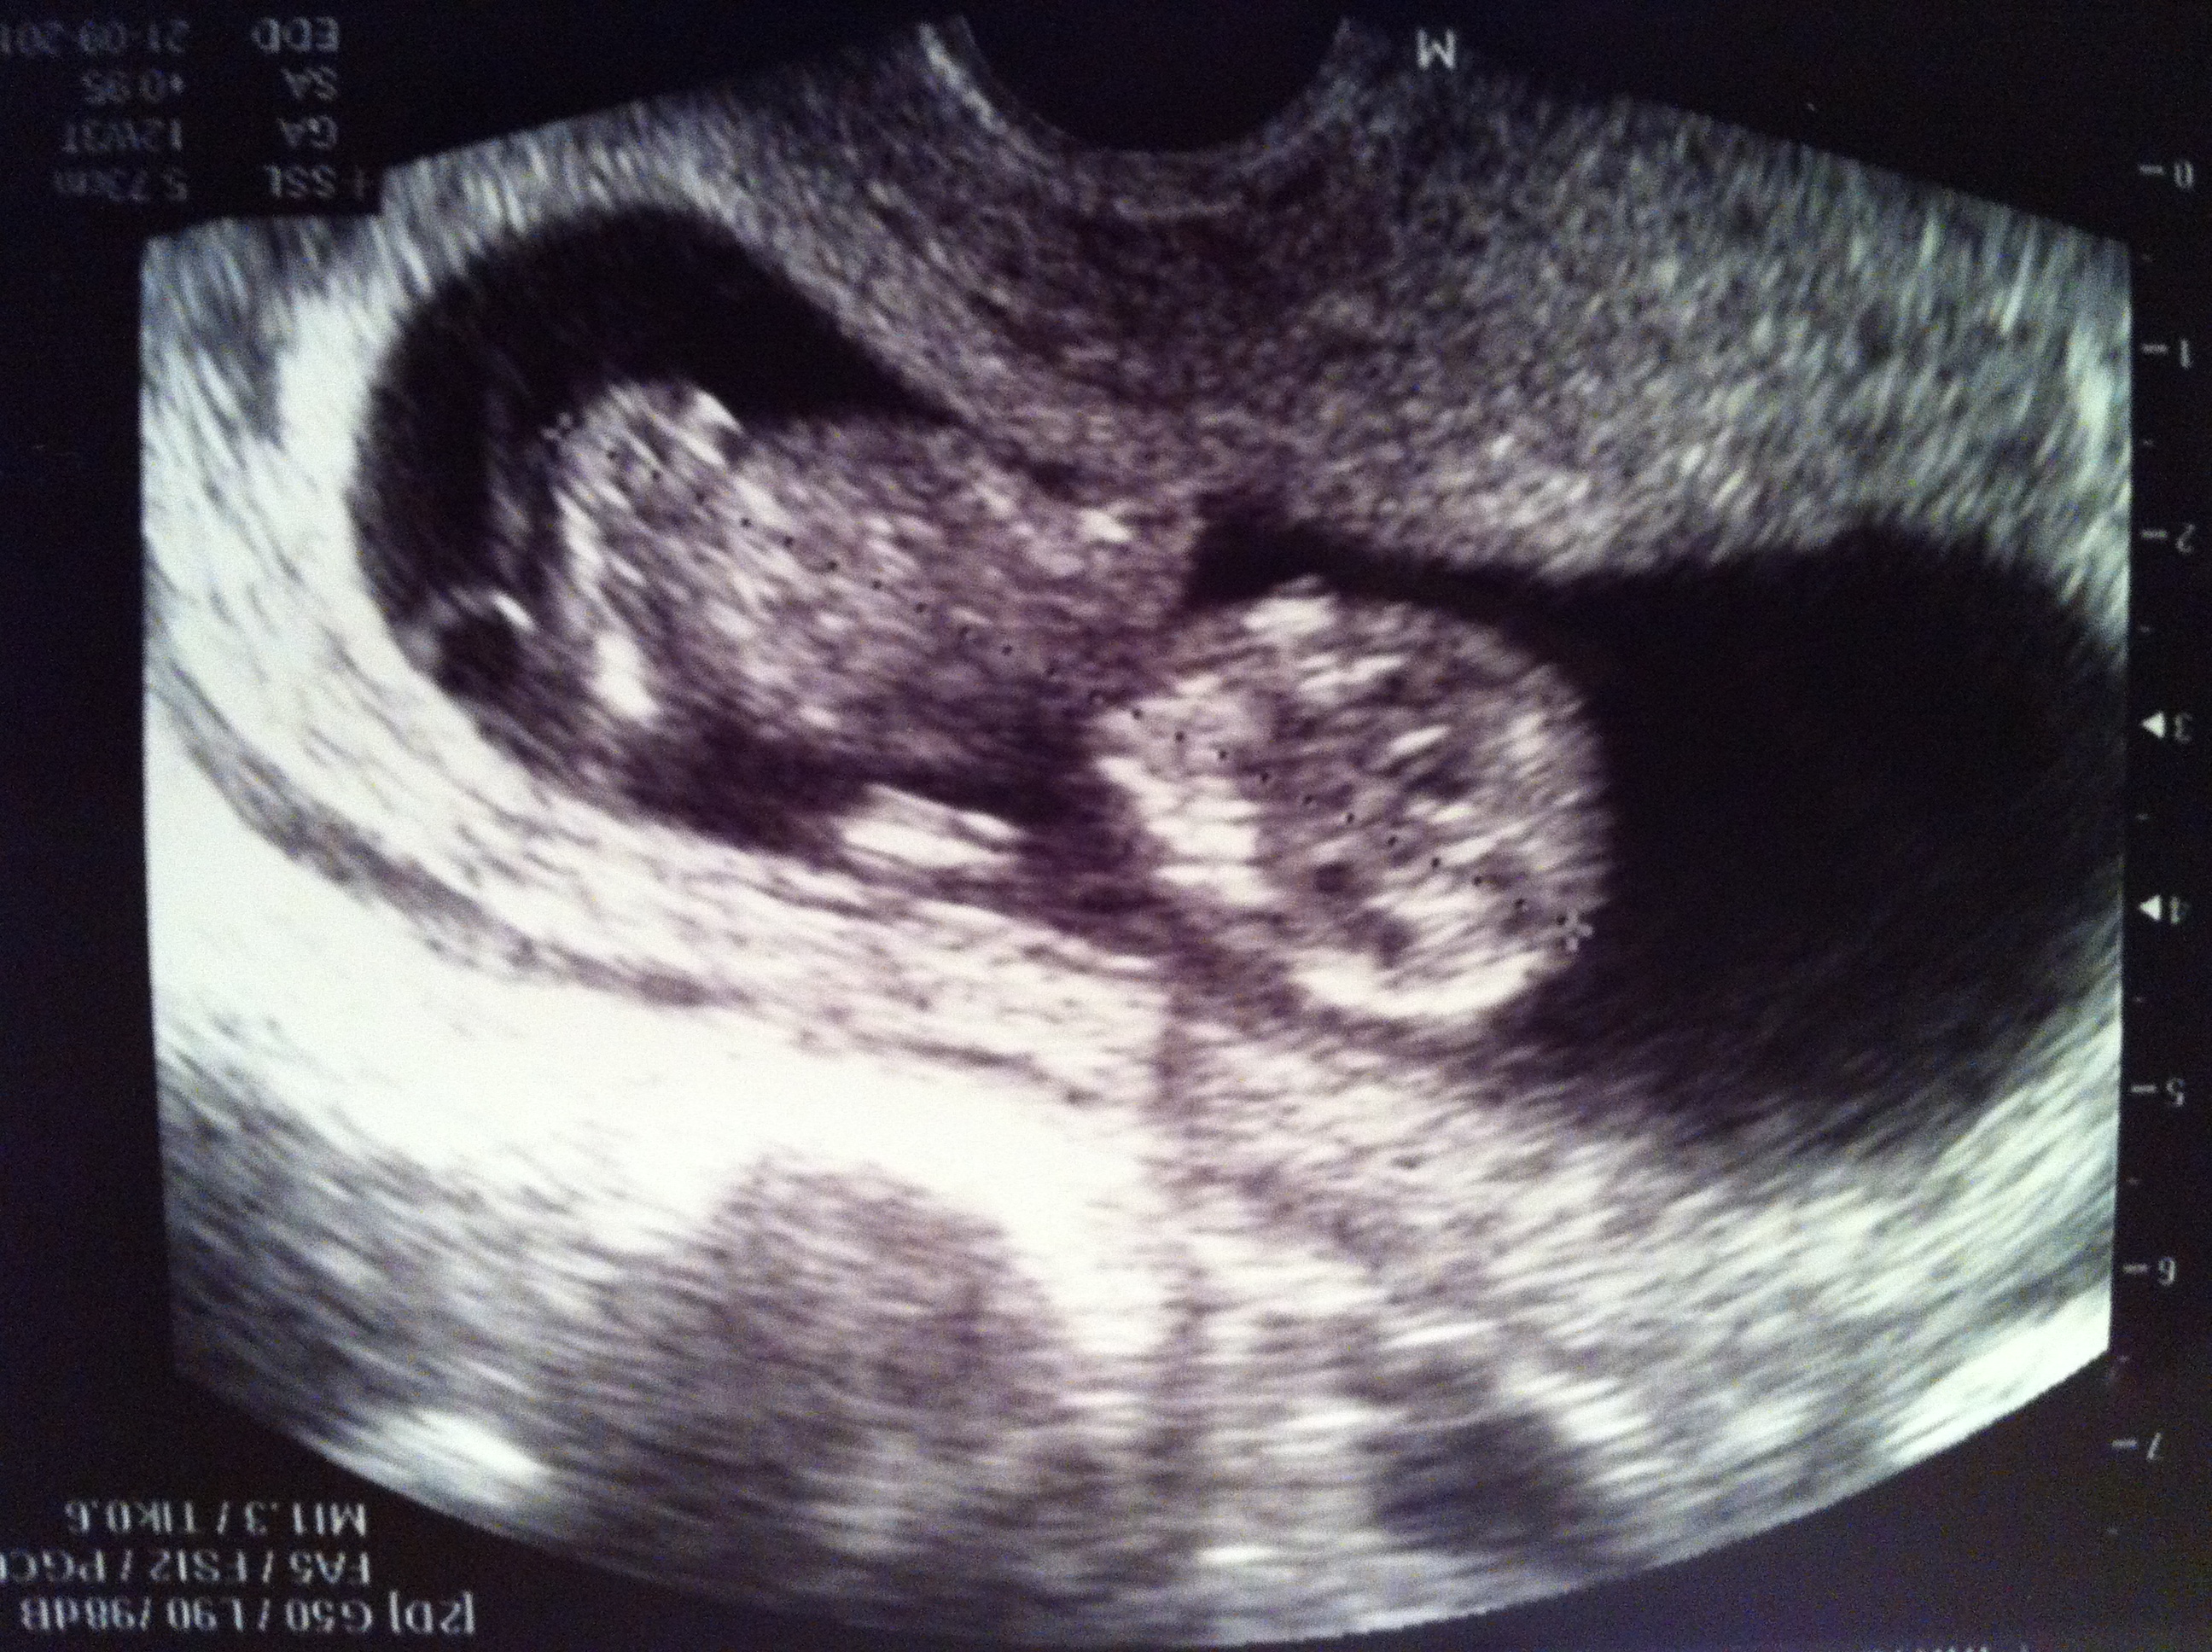

Smiley habe ich den kleinen Wurm in mir genannt, weil es auf dem letzten Ultraschallfoto ein Smiley-Gesicht hat. Oder?